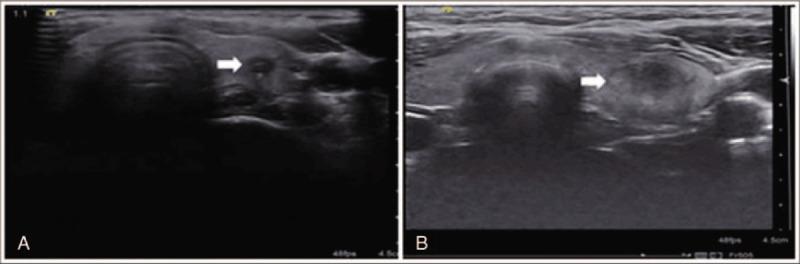

To evaluate the diagnostic efficiency of computer-aided diagnosis (CAD) system and 111 radiologists with different experience in identifying benign and malignant thyroid nodules, and to summarize the ultrasound features that may affect the diagnostic of CAD and radiologists.Fifty thyroid nodules and 111 radiologists were enrolled in this study. All the 50 nodules were diagnosed by the 111 radiologists and the CAD system simultaneously. The diagnostic performance of the CAD system, senior and junior radiologists with the maximum accuracy were calculated and compared. Interobserver agreement for different ultrasound characteristics between the CAD and senior radiologist were analyzed.CAD system showed a higher specificity than junior radiologist (87.5% vs 70.4%, P = .03), and a lower sensitivity than the senior radiologist and junior radiologist but the statistics were not significant (76.9% vs 86.9%, P > .5; 76.9% vs 82.6%, P > .5). The CAD system and senior radiologist got larger AUC than junior radiologist but the differences were not statistically significant (0.82 vs 0.76, respectively; P = .5). The interobserver agreement for the US characteristics between the CAD system and senior radiologist were: substantial agreement for hypoechoic and taller than wide (kappa value = 0.66, 0.78), and moderate agreement for irregular margin and micro-calcifications (kappa value = 0.52, 0.42).The CAD system achieved equal diagnostic accuracy to the senior radiologists and higher accuracy than the junior radiologists. The interobserver agreements in the US features between the CAD system and senior radiologist were substantial agreement for hypoechoic and taller than wide; moderate agreement for irregular margin and micro-calcifications. The location of a thyroid nodule and the feature of macrocalcification with wide acoustic shadow may influence the analysis of the CAD system.

评估计算机辅助诊断(CAD)系统以及111名具有不同经验的放射科医生鉴别甲状腺良恶性结节的诊断效能,并总结可能影响CAD和放射科医生诊断的超声特征。本研究纳入了50个甲状腺结节和111名放射科医生。所有50个结节由111名放射科医生和CAD系统同时进行诊断。计算并比较CAD系统、经验丰富和经验不足的放射科医生的最高诊断准确率。分析CAD系统与经验丰富的放射科医生之间不同超声特征的观察者间一致性。CAD系统显示出比经验不足的放射科医生更高的特异性(87.5%对70.4%,P = 0.03),但敏感性低于经验丰富的放射科医生和经验不足的放射科医生,不过差异无统计学意义(76.9%对86.9%,P > 0.5;76.9%对82.6%,P > 0.5)。CAD系统和经验丰富的放射科医生的曲线下面积(AUC)比经验不足的放射科医生大,但差异无统计学意义(分别为0.82对0.76;P = 0.5)。CAD系统与经验丰富的放射科医生之间超声特征的观察者间一致性为:低回声和纵横比大于1为高度一致(kappa值 = 0.66,0.78);边界不规则和微钙化中度一致(kappa值 = 0.52,0.42)。CAD系统的诊断准确率与经验丰富的放射科医生相当,高于经验不足的放射科医生。CAD系统与经验丰富的放射科医生之间超声特征的观察者间一致性为:低回声和纵横比大于1为高度一致;边界不规则和微钙化中度一致。甲状腺结节的位置以及伴有宽声影的粗大钙化特征可能会影响CAD系统的分析。